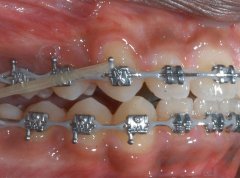

前牙开颌应该怎么办?

前牙开颌是指牙齿在垂直方向上不能咬合,在安氏三种类型的错颌中都可能出现...【详细】